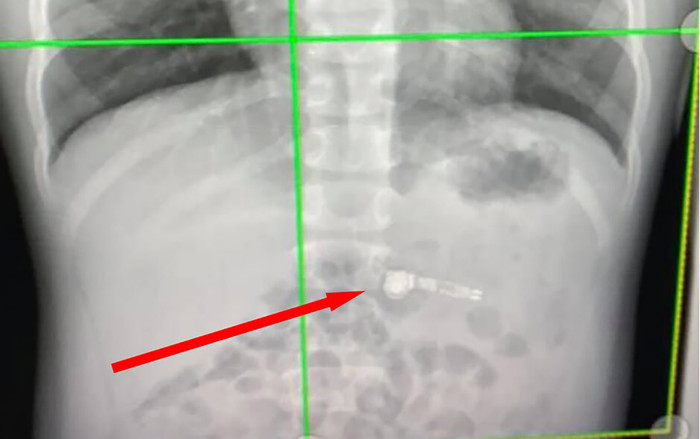

Tại trung tâm nhi khoa Atlanta Egelston, các bác sĩ cũng tỏ ra rất bối rối vì vấn đề mình gặp phải xong hình ảnh chụp X-quang đã phát hiện ra những linh kiện kim loại trong chiếc AirPods và xác nhận rằng đứa trẻ đã nuốt chiếc tai nghe này.